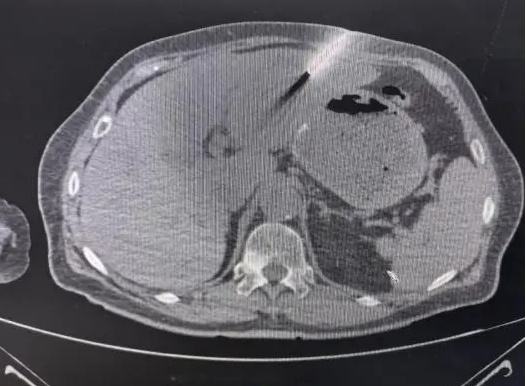

肝穿刺活检是一项关键的微创医疗手段,依赖影像设备的精确指引,通过细针进行精确的穿刺操作。其目的是为了获取病变区域的组织样本,进而进行病理学检测。尤其是在CT引导下进行的肝穿刺活检,该技术展现出其显著的优越性。

在20XX年X月X日的手术中,该技术利用高精度成像技术实现了精确的定位,从而确保了手术的精确度。在手术前,医生通过CT影像对胰头和肝脏的多发病变进行了详细的分析,精确确定了病变的确切位置,并对周边的解剖结构进行了细致的评估。手术期间,CT的实时定位功能确保了穿刺针能够准确穿过肋间,直接到达肿瘤区域,并精确引导至目标病变。在此过程中,操作者巧妙地避开了邻近的关键血管和胆管,成功采集到了病理组织样本。

患者接受了在CT引导下进行的肝脏穿刺活检手术,手术成效显著。术后,患者并未感受到明显的不适,这一现象直接反映了手术的高效性。尤为重要的是,病理检查的结果十分明确。该结果于20XX年X月X日得到了最终的确证。